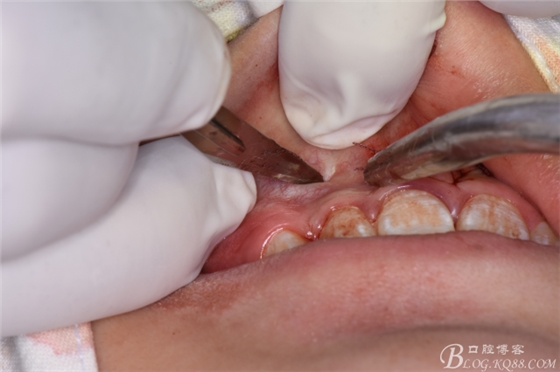

圖6.唇側(cè)局部無痛浸潤麻醉

圖8.先拔除11、21之間多生牙,做唇側(cè)弧形切口